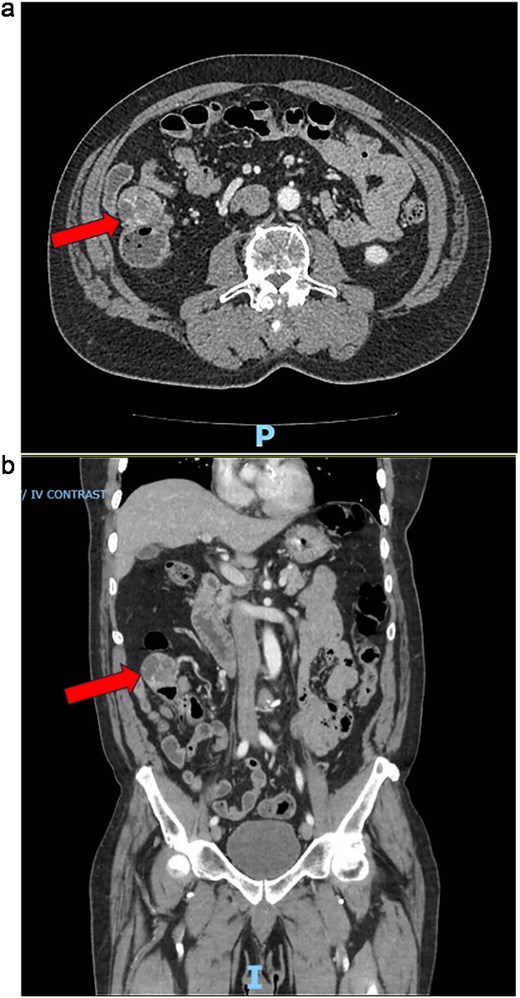

Two years following his MFS diagnosis and treatment, the patient developed new symptoms. After sustaining a fall, the patient complained of persistent weakness, nausea, and anorexia. At the time, the patient was hemodynamically normal and had a normal laboratory evaluation. However, these assessments noted the presence of a 4 cm cecal mass on a CT scan of the abdomen and pelvis (Fig. 1a and b). The patient was admitted for generalized weakness and expedited workup of the cecal mass, which was biopsied and confirmed to be a metastatic MFS. Next-Gen Sequencing completed on this specimen was negative for Cancer Hotspot mutations. A colonoscopy was performed, which showed no other synchronous colonic lesions. However, the colonoscopy identified a submucosal mass located at the ileocecal valve (Fig. 2).

(a) CT abdomen/pelvis axial and coronal views during emergency department presentation with cecal mass seen. (b) CT abdomen/pelvis axial and coronal views during emergency department presentation with cecal mass seen.